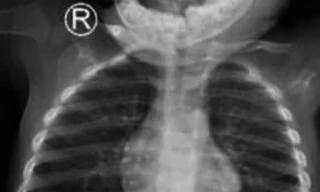

TPO - Trẻ ngậm trong miệng rồi nuốt lúc nào không biết, đến khi đau đớn quằn quại phải nhập viện thì đã bị thủng ruột bởi 2 viên bi nam châm gây ra. Bác sĩ cảnh báo, nuốt dị vật là tai nạn rất nguy hiểm có thể cướp đi sinh mạng của bệnh nhi.